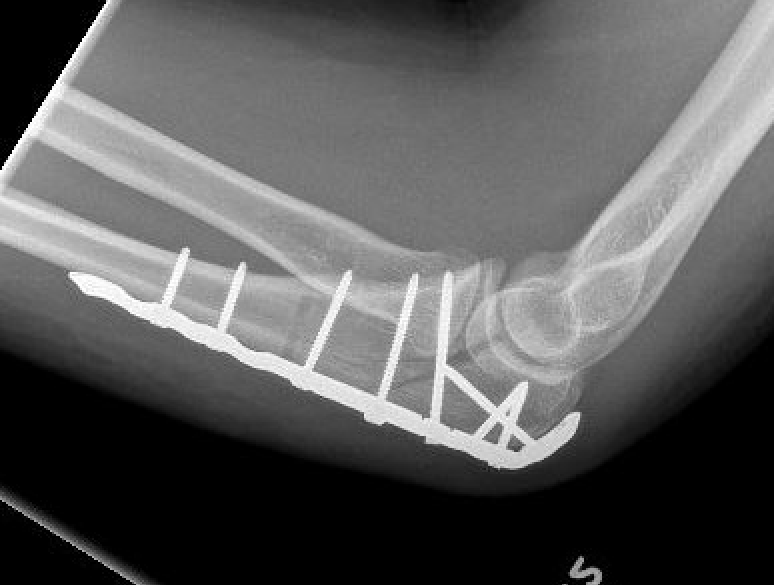

Technique

ORIF olecranon with plate +/- LCL repair

- posterior approach and plate olecranon

- reassess stability

- +/- Kocher approach to LCL and common extensor origin if continued instability

Olecranon plate + ORIF Type II coronoid process + radial head replacement

Olecranon plate with radial head replacement

Olecranon plate with radial head replacement + LCL repair